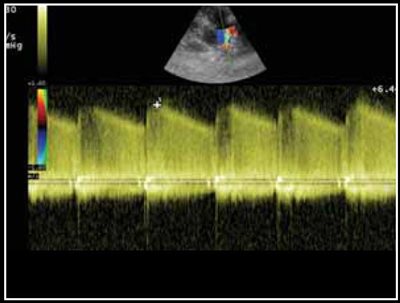

Photo 1 - Persistance du canal artériel visible en mode Doppler couleur sur une vue petit axe transaortique par abord parasternal droit.

Le canal artériel est visualisé dans 96 % des cas en mode bidimensionnel ou en mode Doppler couleur sur une coupe petit axe transaortique par abord parasternal droit (Photo 1), sur une coupe petit axe par abord parasternal crânial gauche (Photo 2), ou plus facilement sur une coupe longitudinale des gros vaisseaux (aorte et tronc pulmonaire) par abord parasternal crânial et dorsal gauche (Photo 3).

Dans la majorité des cas des turbulences importantes sont visibles dans le tronc pulmonaire (Photo 4) [1,2].